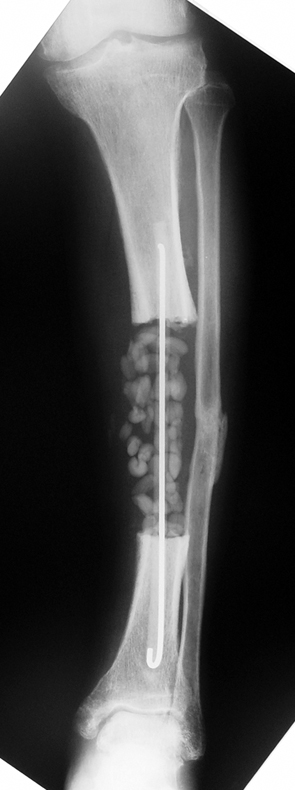

The duration of external fixation (external fixation index) depends on the amount of distraction required, and the extremity is prone to complications during this period. After the distraction phase is completed, the external fixator remains in place during the consolidation phase, which lasts twice as long as the distraction phase; but this period is hardly tolerated. If the external fixator is removed before sufficient consolidation is achieved, fractures, deformity and shortness will be the result. In our department, ‘lenghthening over nail’ method is used in order to decrease the external fixation index and increase patient comfort and activity level. In this method, the intramedullary nail is statically locked after the completion of the distraction phase, and external fixator is removed. The extremity is stabilized by the intramedullary nail during consolidation phase. In this way, complications due to long external fixation index or early removal of the external fixator are avoided.

Case 1